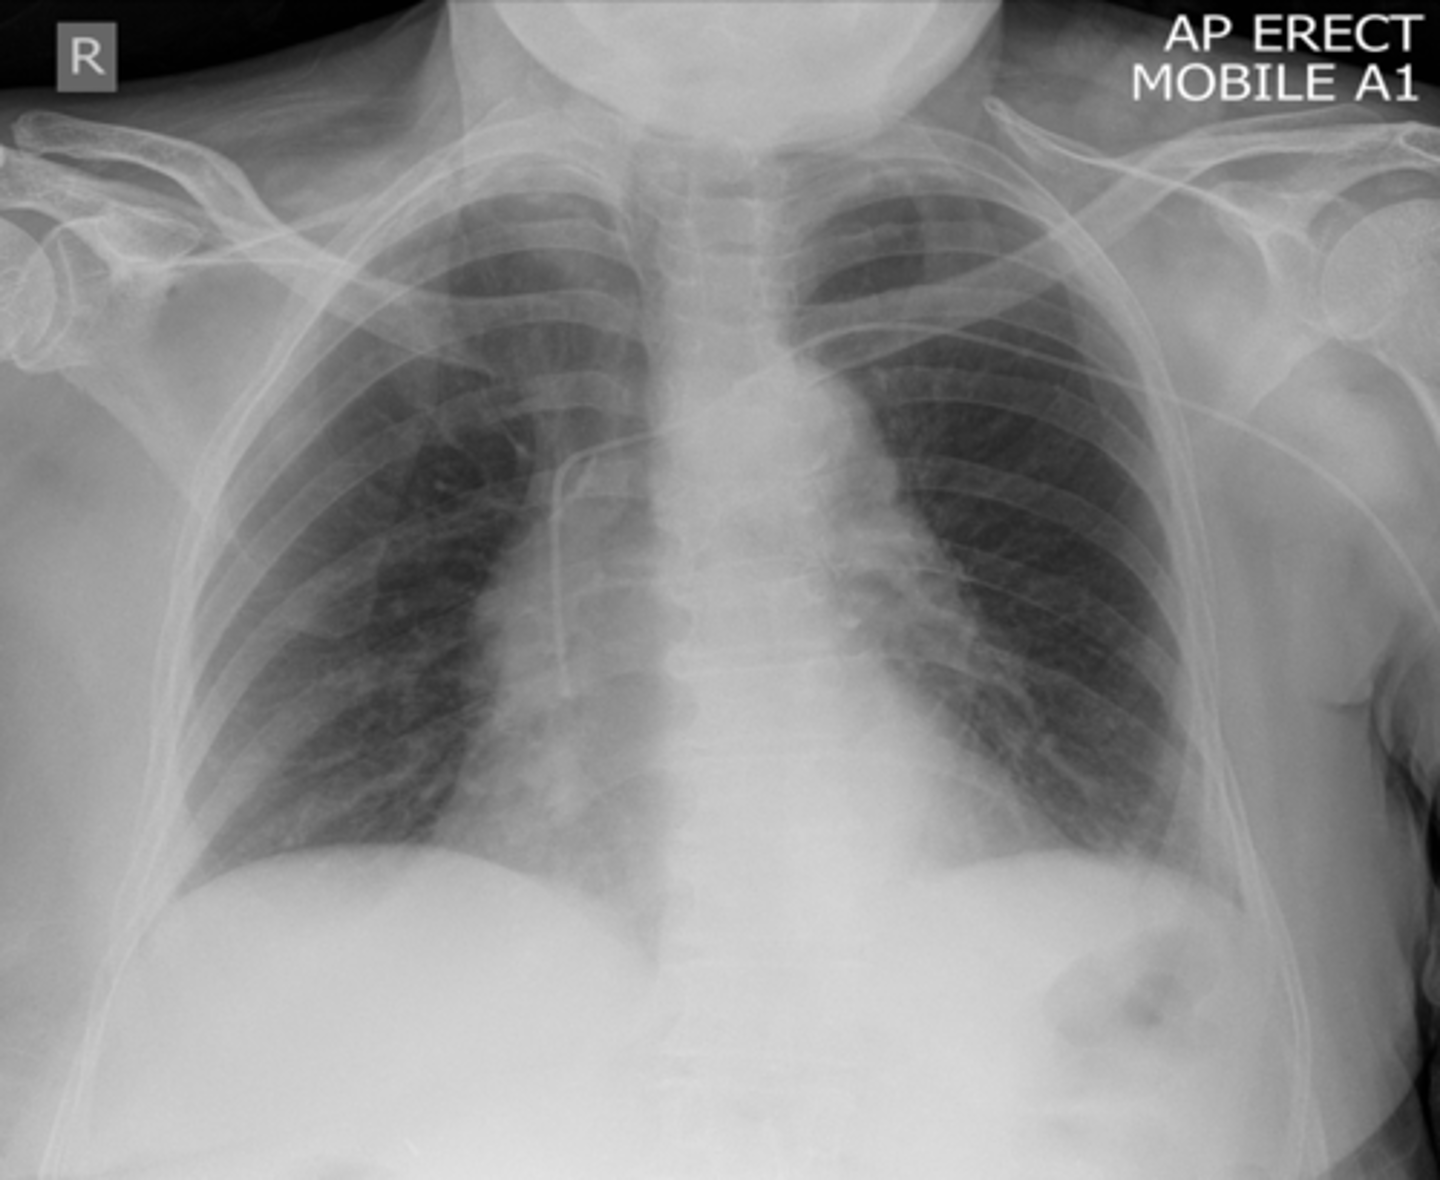

-posteroanterior view -goes from back to front

PA view

-projection: is it in AP or PA view

-most are PA (AP will be labeled)

What does the P stand for in RIPE